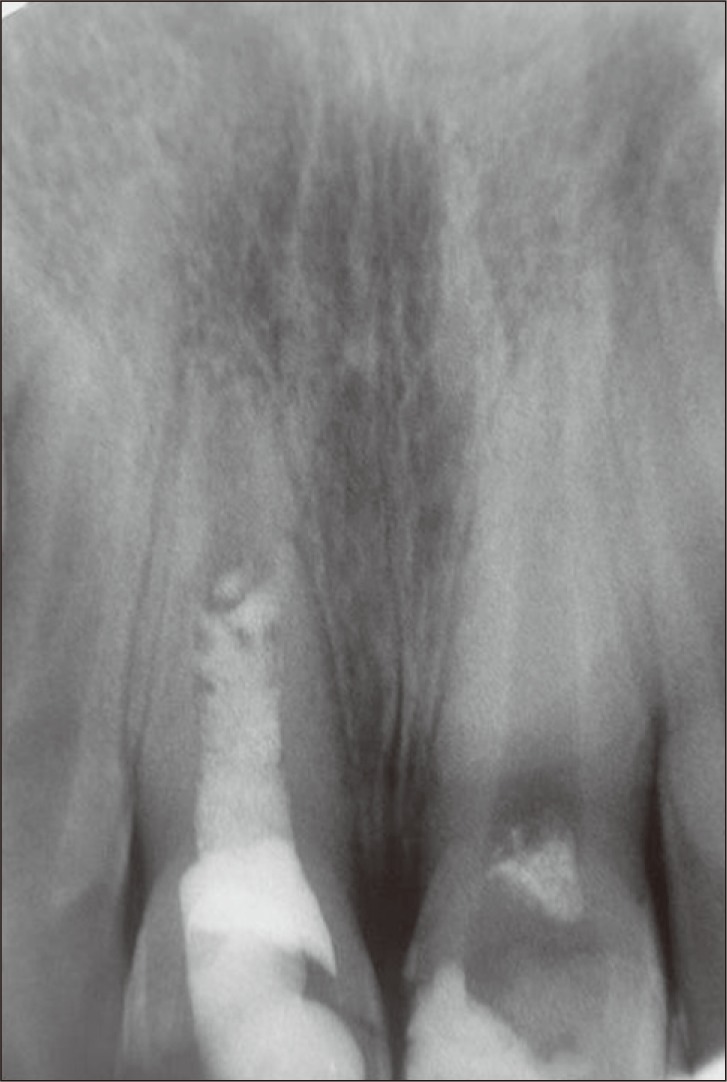

The patient was recalled 6, 12 and 18 months after the treatment. In clinical examination, the teeth were asymptomatic. In radiographic examinations, both teeth showed increased root lengths and apical closure. Root wall thickness had also increased, but the left central incisor showed greater improvements. The radiolucent lesion adjacent to the right central incisor had healed (Figures 2 and 3).